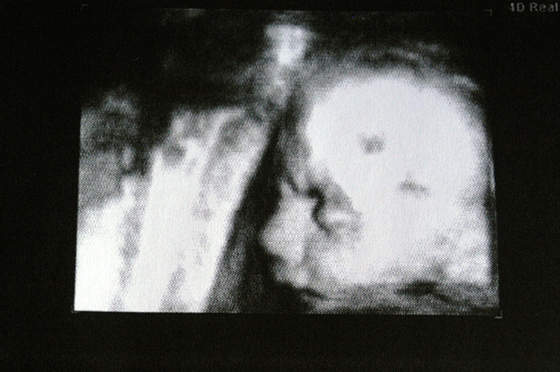

To Lilianka w 25tc, waga 806g.

ale się schował. Drobniutki ten nosek,moja ma kluche ;-) Widać różnice między dziećmi na tym usg 3d chyba faktycznie kłamią

A tak jak już pisalam na głónym, na tych zdjęciach Lilka wyglada identycznie ja Olimpia.